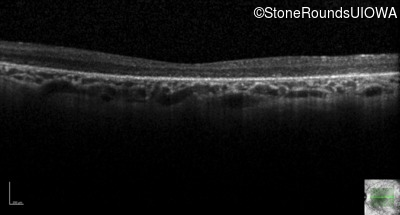

Optical Coherence Tomography - Left - 10/180 sc

Exemplar / OCT Stack